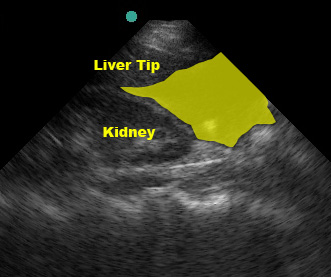

Although Morrison’s pouch is the most dependent (“deepest”) space in the supine patient, blood from elsewhere in the abdomen may not yet have tracked into Morrison’s pouch. If blood is going to seep into this area, it will flow through the paracolic gutter past the tip of the liver. Thorough evaluation of the RUQ includes visualizing the inferior tip of the liver as fluid may collect in this area instead of (or prior to) Morrison’s pouch.

(Figure 23/23.1)